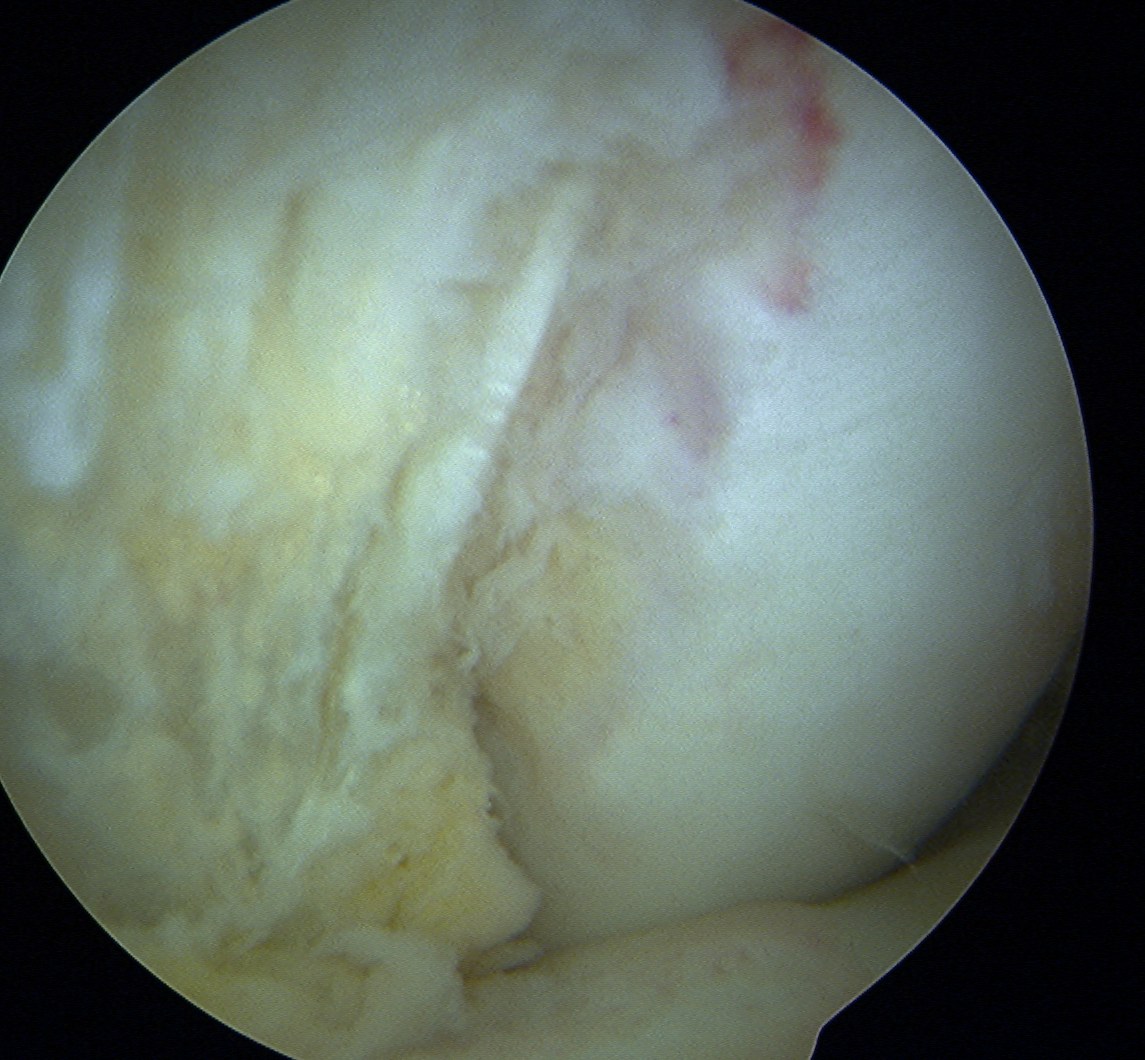

Cruciate ligament ganglion

Technique

Surgical technique PDF using trans-septal portal

- 85 intra-articular ganglions

- 49 ACL, 16 PCL

- 12 from anterior horn meniscus, 3 posterior horn meniscus

- 3 from fat pad

Technique

Surgical technique PDF using trans-septal portal